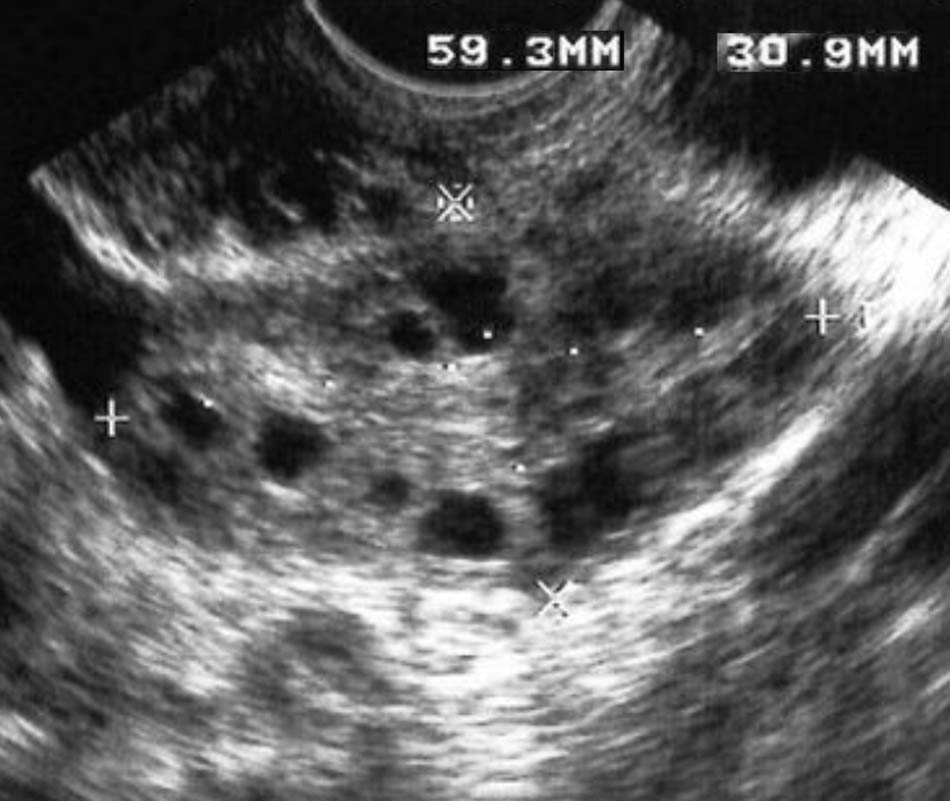

FDP is an essential feature of PCOS. The follicles might be scattered throughout the ovary or distributed peripherally around the ovarian stroma. The first variant is considered normal, and the second is the so-called ultrasonographic “string of pearls” sign, a typical finding in PCOS (Figure 1) [39].

Transverse US image of the left ovary demonstrates the “string of pearls” sign.